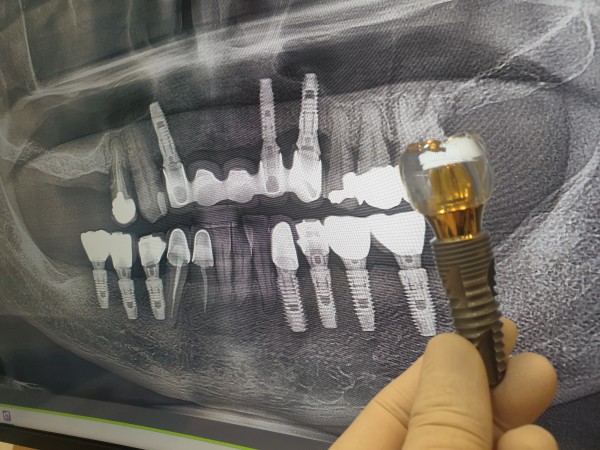

네비게이션 임플란트는 수술 성공률을 높이기 위해

천안 백년치과에서는 보다 특화된 치료 시스템을 진행합니다.

CT영상을 이용해 주변 치아와의 간격, 잇몸뼈의 상태, 신경 분포 등

3차원 모델로 구현해 최적의 임플라트 식립 위치를 결정하고

위치, 각도, 식립위치까지 정확하게 진행됩니다.